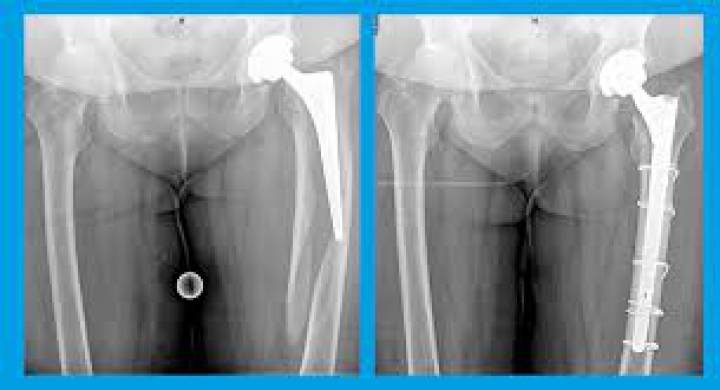

Als een osteosynthese of een gewrichtsprothese volgt, betekent dat een operatieve behandeling in de operatiezaal, in opname of dagziekenhuis, waarbij pinnen, schroeven, platen, cerclagedraden, externe fixateur of intramedullaire (intraosseuze) nagels, al dan niet een (meestal schouder- of heup-) prothese.

Door de veroudering van de bevolking en een lagere drempel om versleten gewrichten (vooral heup, knie en schouder) te vervangen door een prothese, komt de laatste jaren een ander fenomeen in de zin van fracturen rond de protheses, of periprosthetische fracturen genoemd. Deze resulteren vaak in een moeilijke therapeutische uitdaging en in een zwaardere chirurgie.